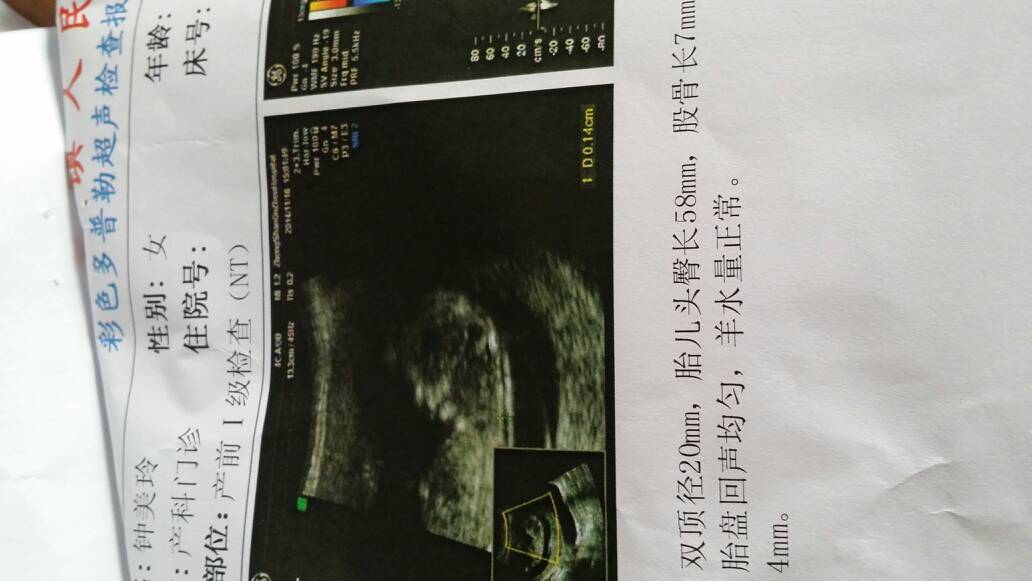

今天的检查结果,好开心,一切正常 今天的检查结果,好开心,一切正常😊 点击展开 ZML 2014-11-16 17:57 为您推荐: 其他回答 你好,首先恭喜准妈妈了,在接下来的孕期里,你要保持良好的心态,有助于胎宝宝健康发育。 命中苦乐 2014-11-16 19:36 恭喜宝妈,注意休息 荧宝宝的妈 2014-11-16 19:13 祝宝妈好孕!! 幸福在手心 2014-11-16 18:06 恭喜。宝妈好孕 成成麻麻 2014-11-16 18:02 恭喜你,好当然是最好不过了,凡事只求好,顺利了。 艾米儿的世界 2014-11-16 18:02 加载更多 相关问题 怀孕八个月了,今天检查一切正常,好开心宝宝健康 好开心好开心,前几个星期去检查未见胎芽,今天去检查一切都好 今天出满月了,好开心!